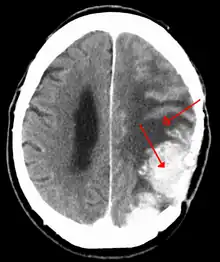

A contrast-enhanced CT scan of the brain, demonstrating the appearance of a meningioma

A meningioma that previously had been operated on, with surrounding edema

Meningiomas are visualized readily with contrast CT, MRI with gadolinium,[17] and arteriography, all attributed to the fact that meningiomas are extra-axial and vascularized. CSF protein levels are usually found to be elevated when lumbar puncture is used to obtain spinal fluid.